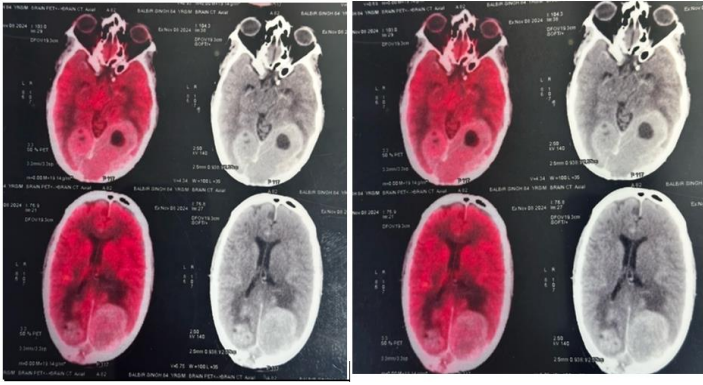

• A PET-CT performed on 8th November 2024 revealed a mass in the distal body of the stomach, bilateral lung metastases, and bilateral occipital lobe masses accompanied by perilesional edema and a midline shift.(Fig.2)

FIG 2: PET CT SCAN NOV 24

Figure 2